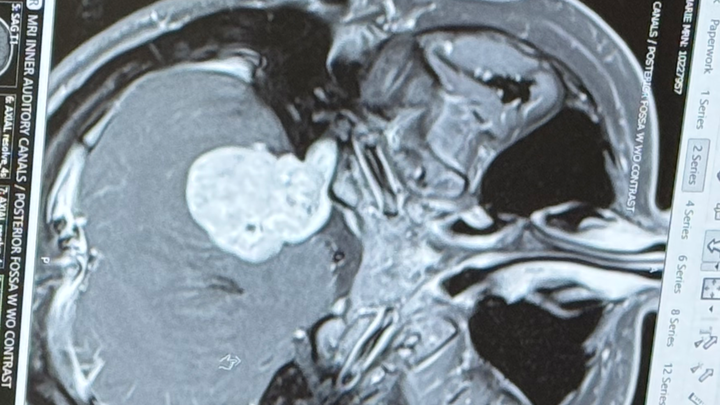

Hello, friends and family. My wife, Bre, and the mother of my kids went into the ER yesterday for ear pressure and found out that she has a big tumor.

It is not cancerous, but she does need surgery, and it's a 12-18 hour surgery with a three-month recovery time. Bre and I will be off work for three months and need help with monthly bills for our house, groceries, etc.